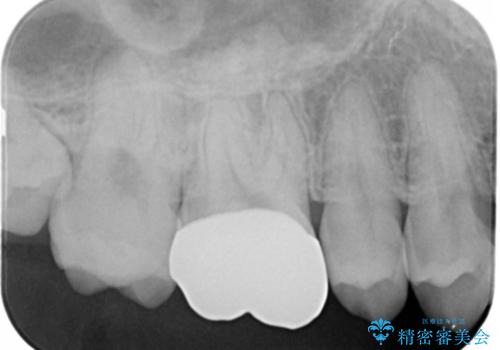

銀歯を白くしたい フルジルコニアクラウンとセラミックインレー

切削量・形態を考慮し、上はセラミッククラウン、下はセラミックインレーでの治療を選択しました。

- 176000円(フルジルコニアクラウン、仮歯、セラミックインレー)費用は治療当時の料金となります

上はう蝕が歯頚部まで達していたのでクラウンでの治療を選択しました。

下はクラウンほど切削量が多くないと判断し、インレーでの治療を選択しました。